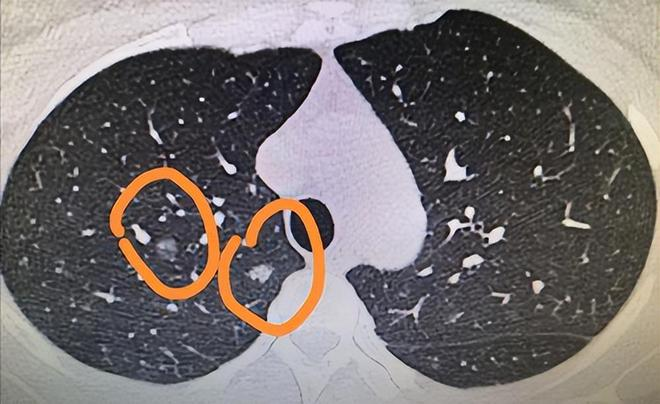

肺部结节的症状有哪些

肺部结节的症状与其性质大小部位有关,具体症状如下感染性结节可能出现发热咳嗽等症状小结节和微小结节大多数为良性病变,一般不会引起任何症状,仅在体检时被发现直径大于1cm的结节特别是邻近支气管或位于支气管内的结节,可能出...